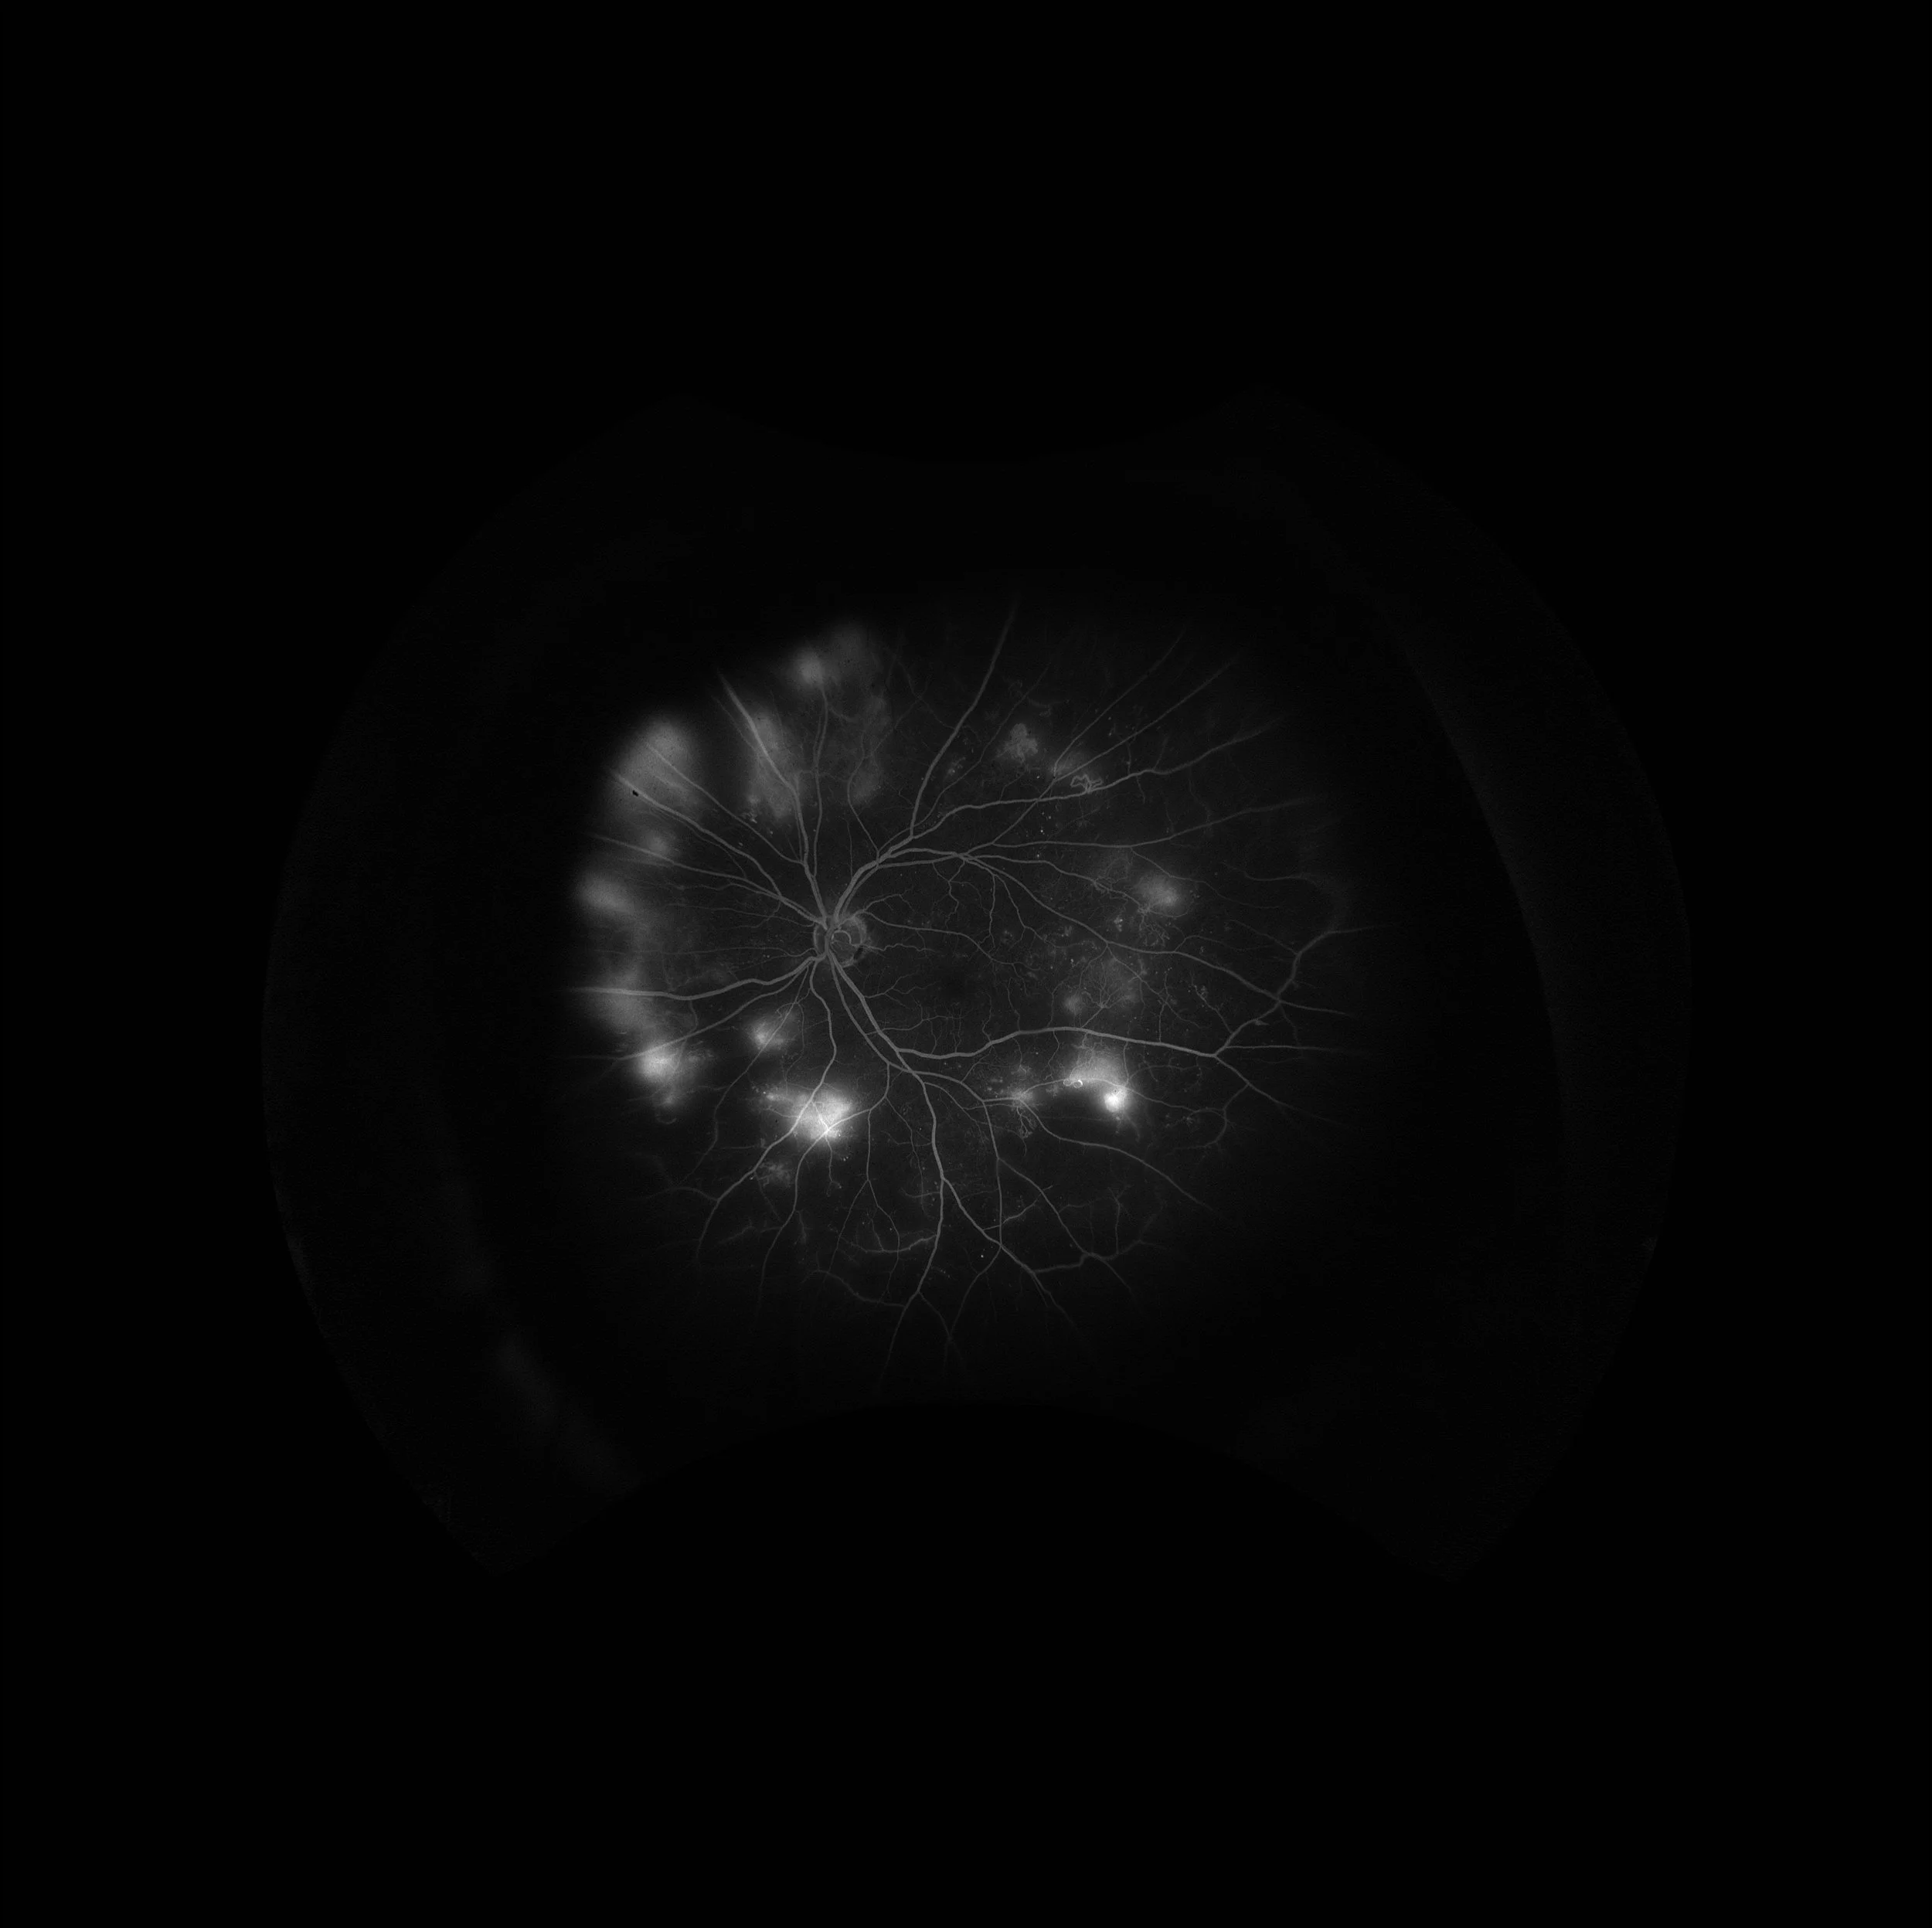

Case #1: 82F, Flashes and Floaters